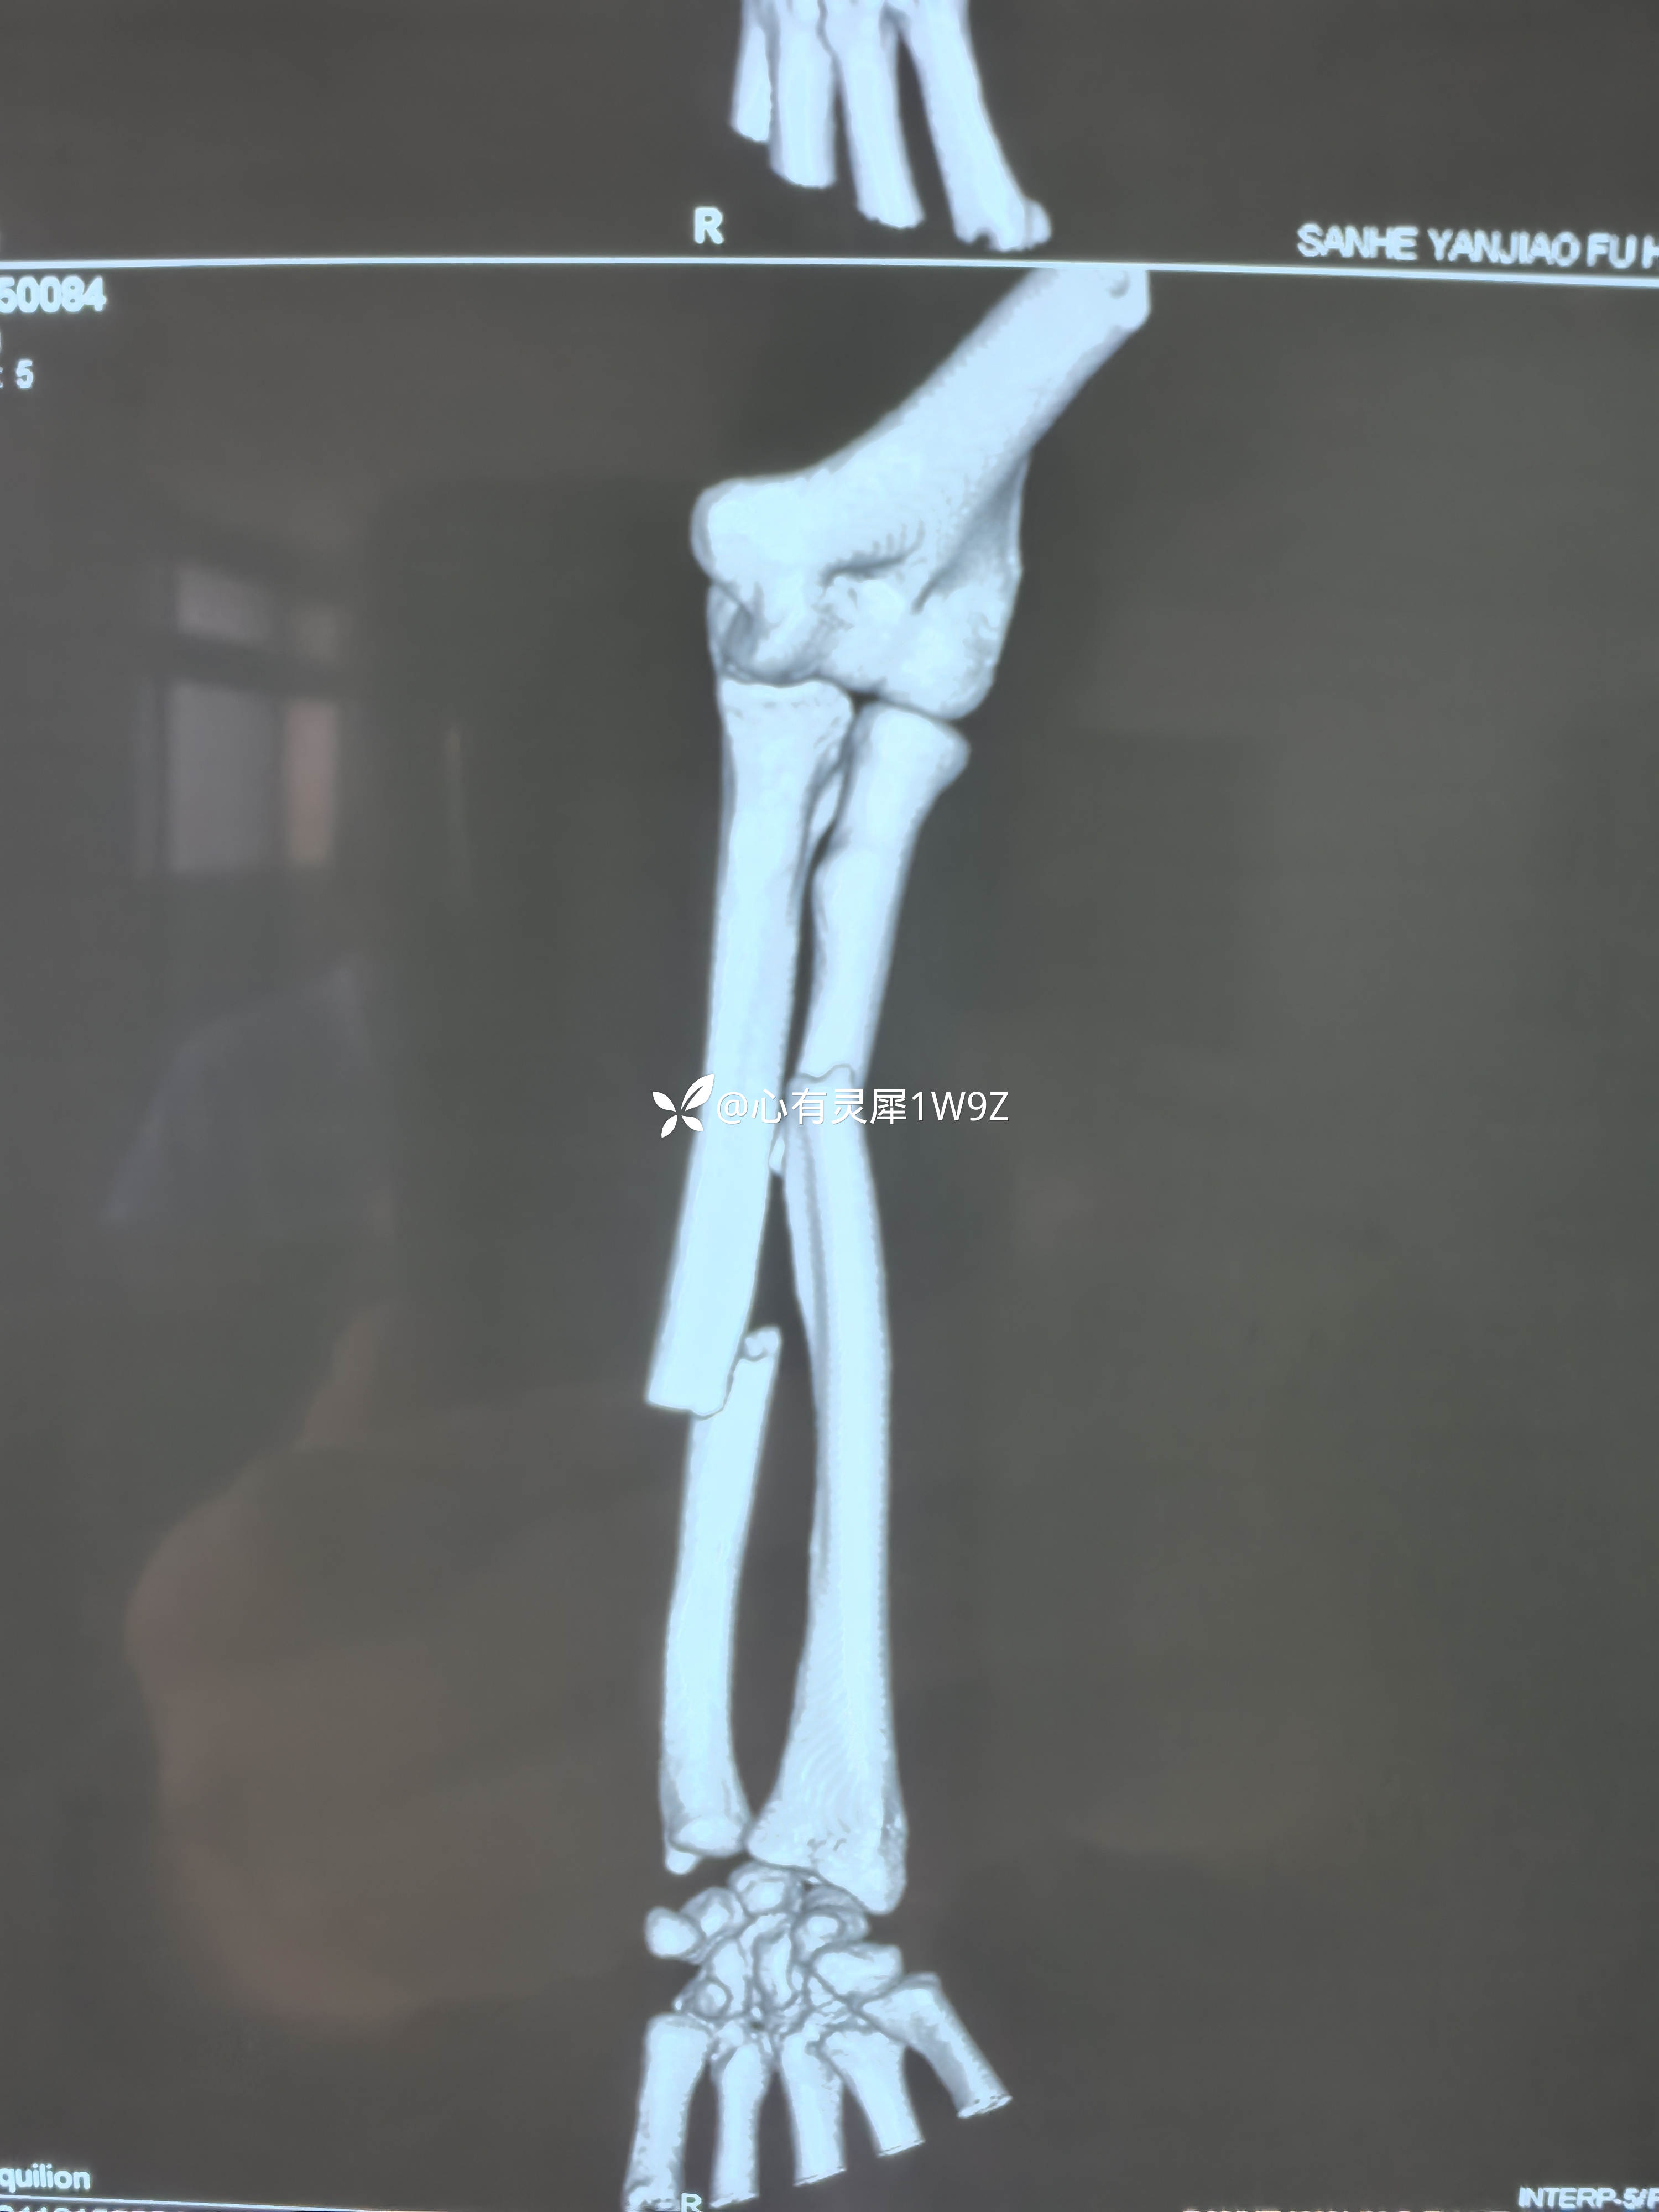

尺桡骨双骨折钢板内固定

【临床诊断】:左侧尺桡骨双骨折